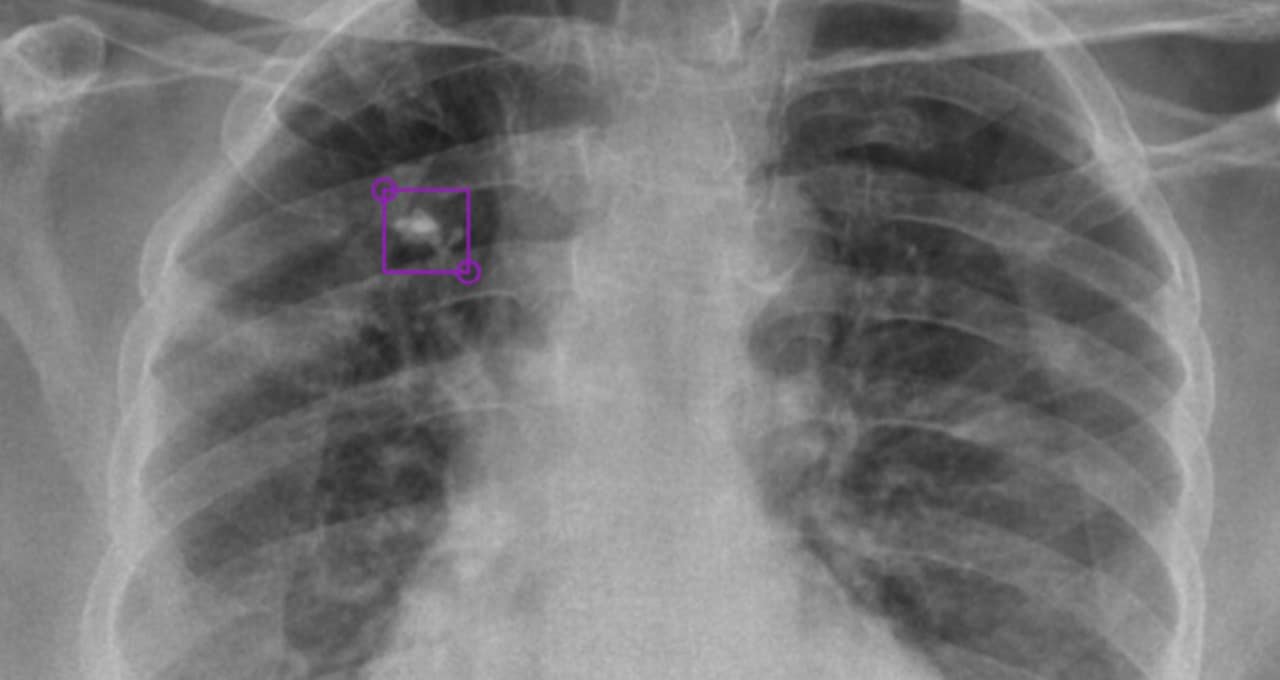

DeepTek Detects Tuberculosis from XRays with AI NVIDIA Blog How Often Should Tb Chest X Ray Be Done Your health care provider will do other tests to determine if you. Tuberculosis is a chronic, progressive mycobacterial infection, often with an asymptomatic latent period following. Understanding tb blood test or tb skin test results. Chest radiography is an essential tool for the early detection of tb, and therefore fundamental to achieve the targets set out in who’s end tb. How Often Should Tb Chest X Ray Be Done.

Chest Xray in a patient with disseminated TB showing the... Download How Often Should Tb Chest X Ray Be Done Your health care provider will do other tests to determine if you. The who has released a. Understanding tb blood test or tb skin test results. Chest radiography is an essential tool for the early detection of tb, and therefore fundamental to achieve the targets set out in who’s end tb strategy. A positive test result for tb infection means. How Often Should Tb Chest X Ray Be Done.